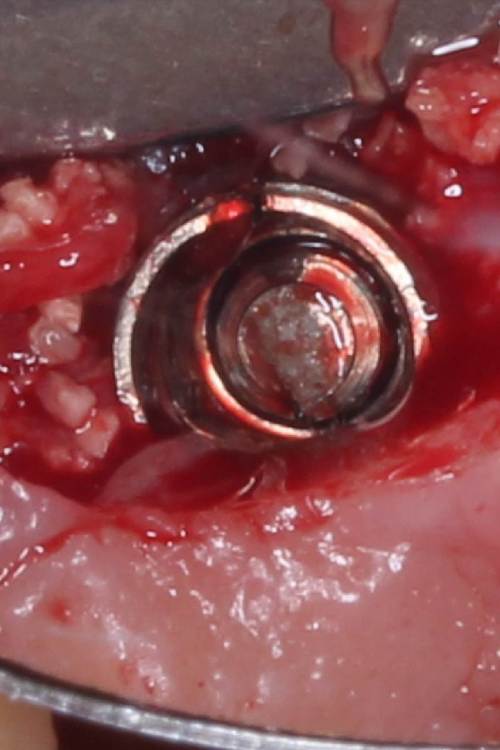

АнтонТЛТ Опубликовано 4 июня, 2021 Поделиться Опубликовано 4 июня, 2021 Жил да был имплантат 3.5мм, прижимался хорошо вместе с поджсаженной костью. Но в один момент ортопед со злобным техником решили его запротезтровать неоригинальным тибейсом в составе цирконевого моста. Имплантату это не понравилось и он решил, что ему пора на покой. И сделал себе харакири. А чтобы не сильно травмировать пациента, было решено удалить винт и имплантат. Затем сразу же поставить имплантат чуть короче и немного потолще. Время работы 50минут с учётом фотографий. 3 Ссылка на комментарий

Irouil Опубликовано 4 июня, 2021 Поделиться Опубликовано 4 июня, 2021 Винт, насколько я понимаю, удалялся реверсивным сверлом. А чем удалялся сам имплант? Ссылка на комментарий

АнтонТЛТ Опубликовано 4 июня, 2021 Автор Поделиться Опубликовано 4 июня, 2021 1 час назад, Irouil сказал: Винт, насколько я понимаю, удалялся реверсивным сверлом. А чем удалялся сам имплант? Fr-kit neobiotech 1 Ссылка на комментарий